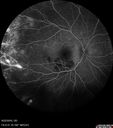

Coats' Disease - 14 year old - Asymptomatic499 viewsPresented with macular exudates. Temporal macroaneurysms responded to laser. Ultra-wide field FA shows nonperfusionNov 07, 2016